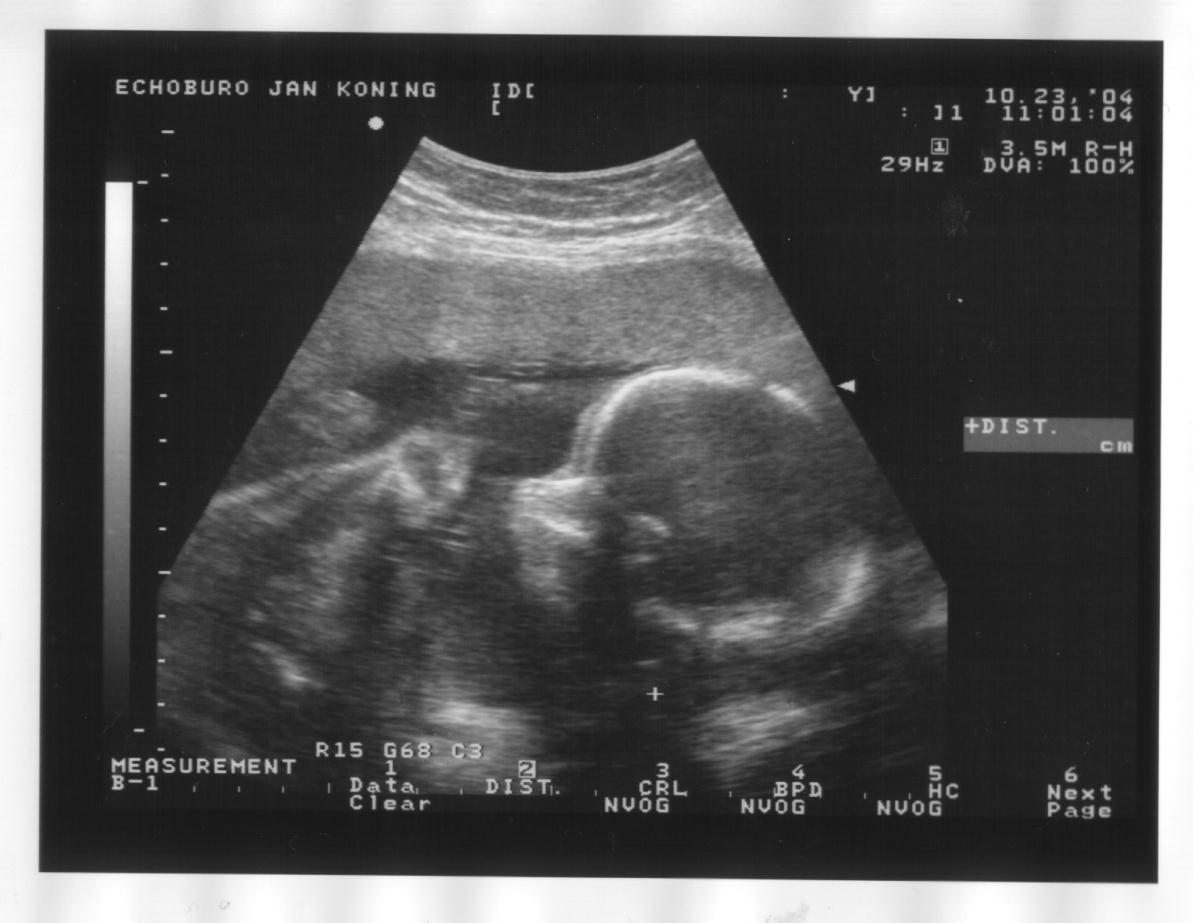

23 oktober 2004

Zijaanzicht hoofd, handje bij het gezicht en oog, bovenste helft borst, opgetrokken knietjes